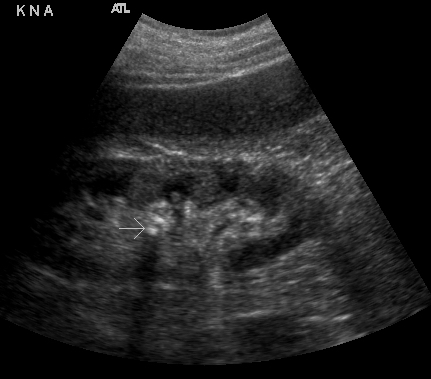

- Figures 5 and 6. Renal stones (arrows) with shadowing

- Stones at the ureteropelvic junction - look for a bright object that casts a shadow at the hilum as the renal pelvis narrows to form the ureter.

- Stones more distal in the ureter are often hard to identify.1 If you can, follow the dilated ureter down toward the bladder. A bright object that casts a shadow within the ureter or at the junction of the bladder is consistent with ureteral stone.

- Figure 7. Stone in the mid-ureter in setting of hydroureter (Courtesy of Dasia Esener, MD)